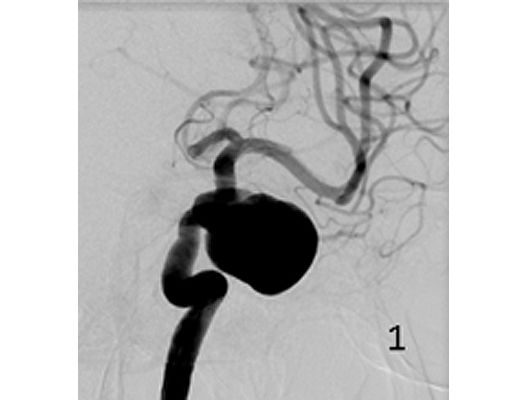

Aneurysmen an der Gefäßen des Gehirns können in vielen Fällen minimalinvasiv durch einen Zugang durch das Gefäßsystem, zumeist von der Leiste aus behandelt werden (sog. Endovaskuläre Therapie). Dabei gibt es z.B. die Möglichkeit ein Aneurysma durch Einbringung von Platinspiralen zu verschließen (sog. Coiling). Auch für komplexe Aneurysmen stehen inzwischen verschiedene endovaskuläre Methoden zur Verfügung.

Das Beispiel zeigt die angiographischen Bilder einer Patientin, bei der es zu einer Sehstörung gekommen war. Die Ursache war ein großes Aneurysma der Halsschlagader an der Schädelbasis (Bild 1). Bild 2 zeigt die Lage des Aneurysmas hinter dem Auge. Durch den Druck des Aneurysmas auf den Sehnerv war es zu der Sehstörung gekommen. Die Patientin wurde mit einer speziellen Gefäßprothese versorgt, welche über eine Punktion der Leistenarterie in die Halsschlagader eingesetzt wurde (Bild 3). Bei der Kontrolle nach 6 Monaten zeigte sich ein vollständiger Verschluss des Aneurysmas (Bild 4). Die Sehstörung hatte sich vollständig zurückgebildet.